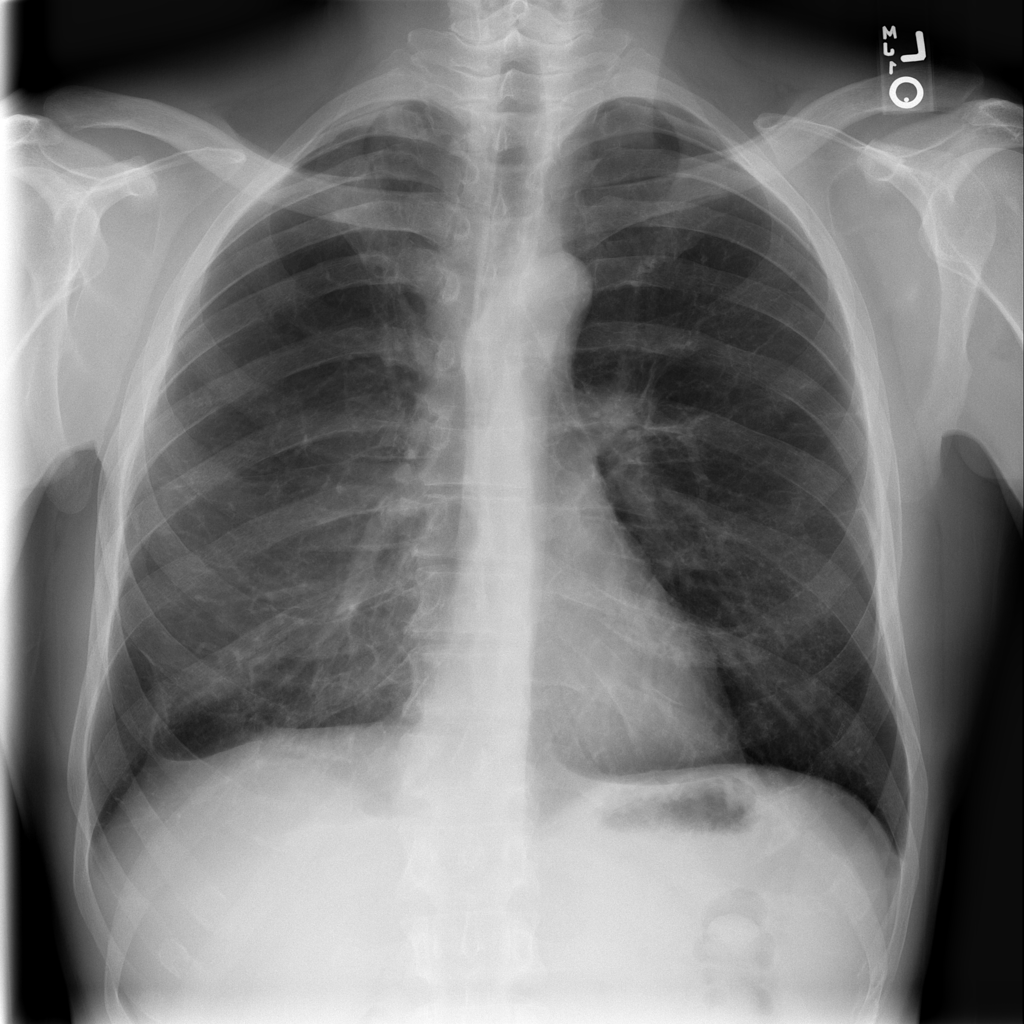

PAT-894B · IMG-000Emphysema

PAT-894B · IMG-000

PA